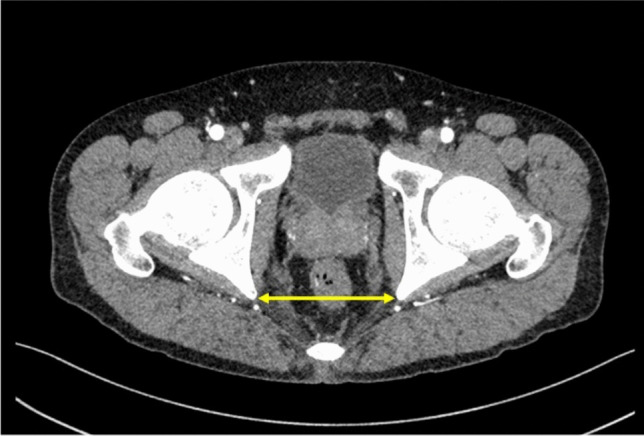

Methods: We prospectively enrolled patients with UC scheduled for two-stage restorative proctocolectomy with a preoperative plan for hand-sewn IPAA. Patients were categorized into a conversion group that required conversion to stapled IPAA intraoperatively and a non-conversion group. Preoperative visceral fat area and anatomical indicators were measured using computed tomography (CT). Logistic regression analysis was performed to identify predictors of conversion surgery.

Results: A total of 106 patients were included, with 12 (11.3%) in the conversion group. Compared with those in the non-conversion group, patients in the conversion group had significantly higher body mass index (BMI), greater visceral fat, and a longer distance between the ileal end and the anal verge (p < 0.01). Logistic regression identified visceral fat (per 10 cm2 increase: odds ratio [OR] 1.19, 95% confidence interval [CI] 1.02-1.39, p = 0.01) as a significant predictor of conversion surgery, whereas BMI was not (OR 1.03, 95% CI 0.77-1.21, p = 0.72).